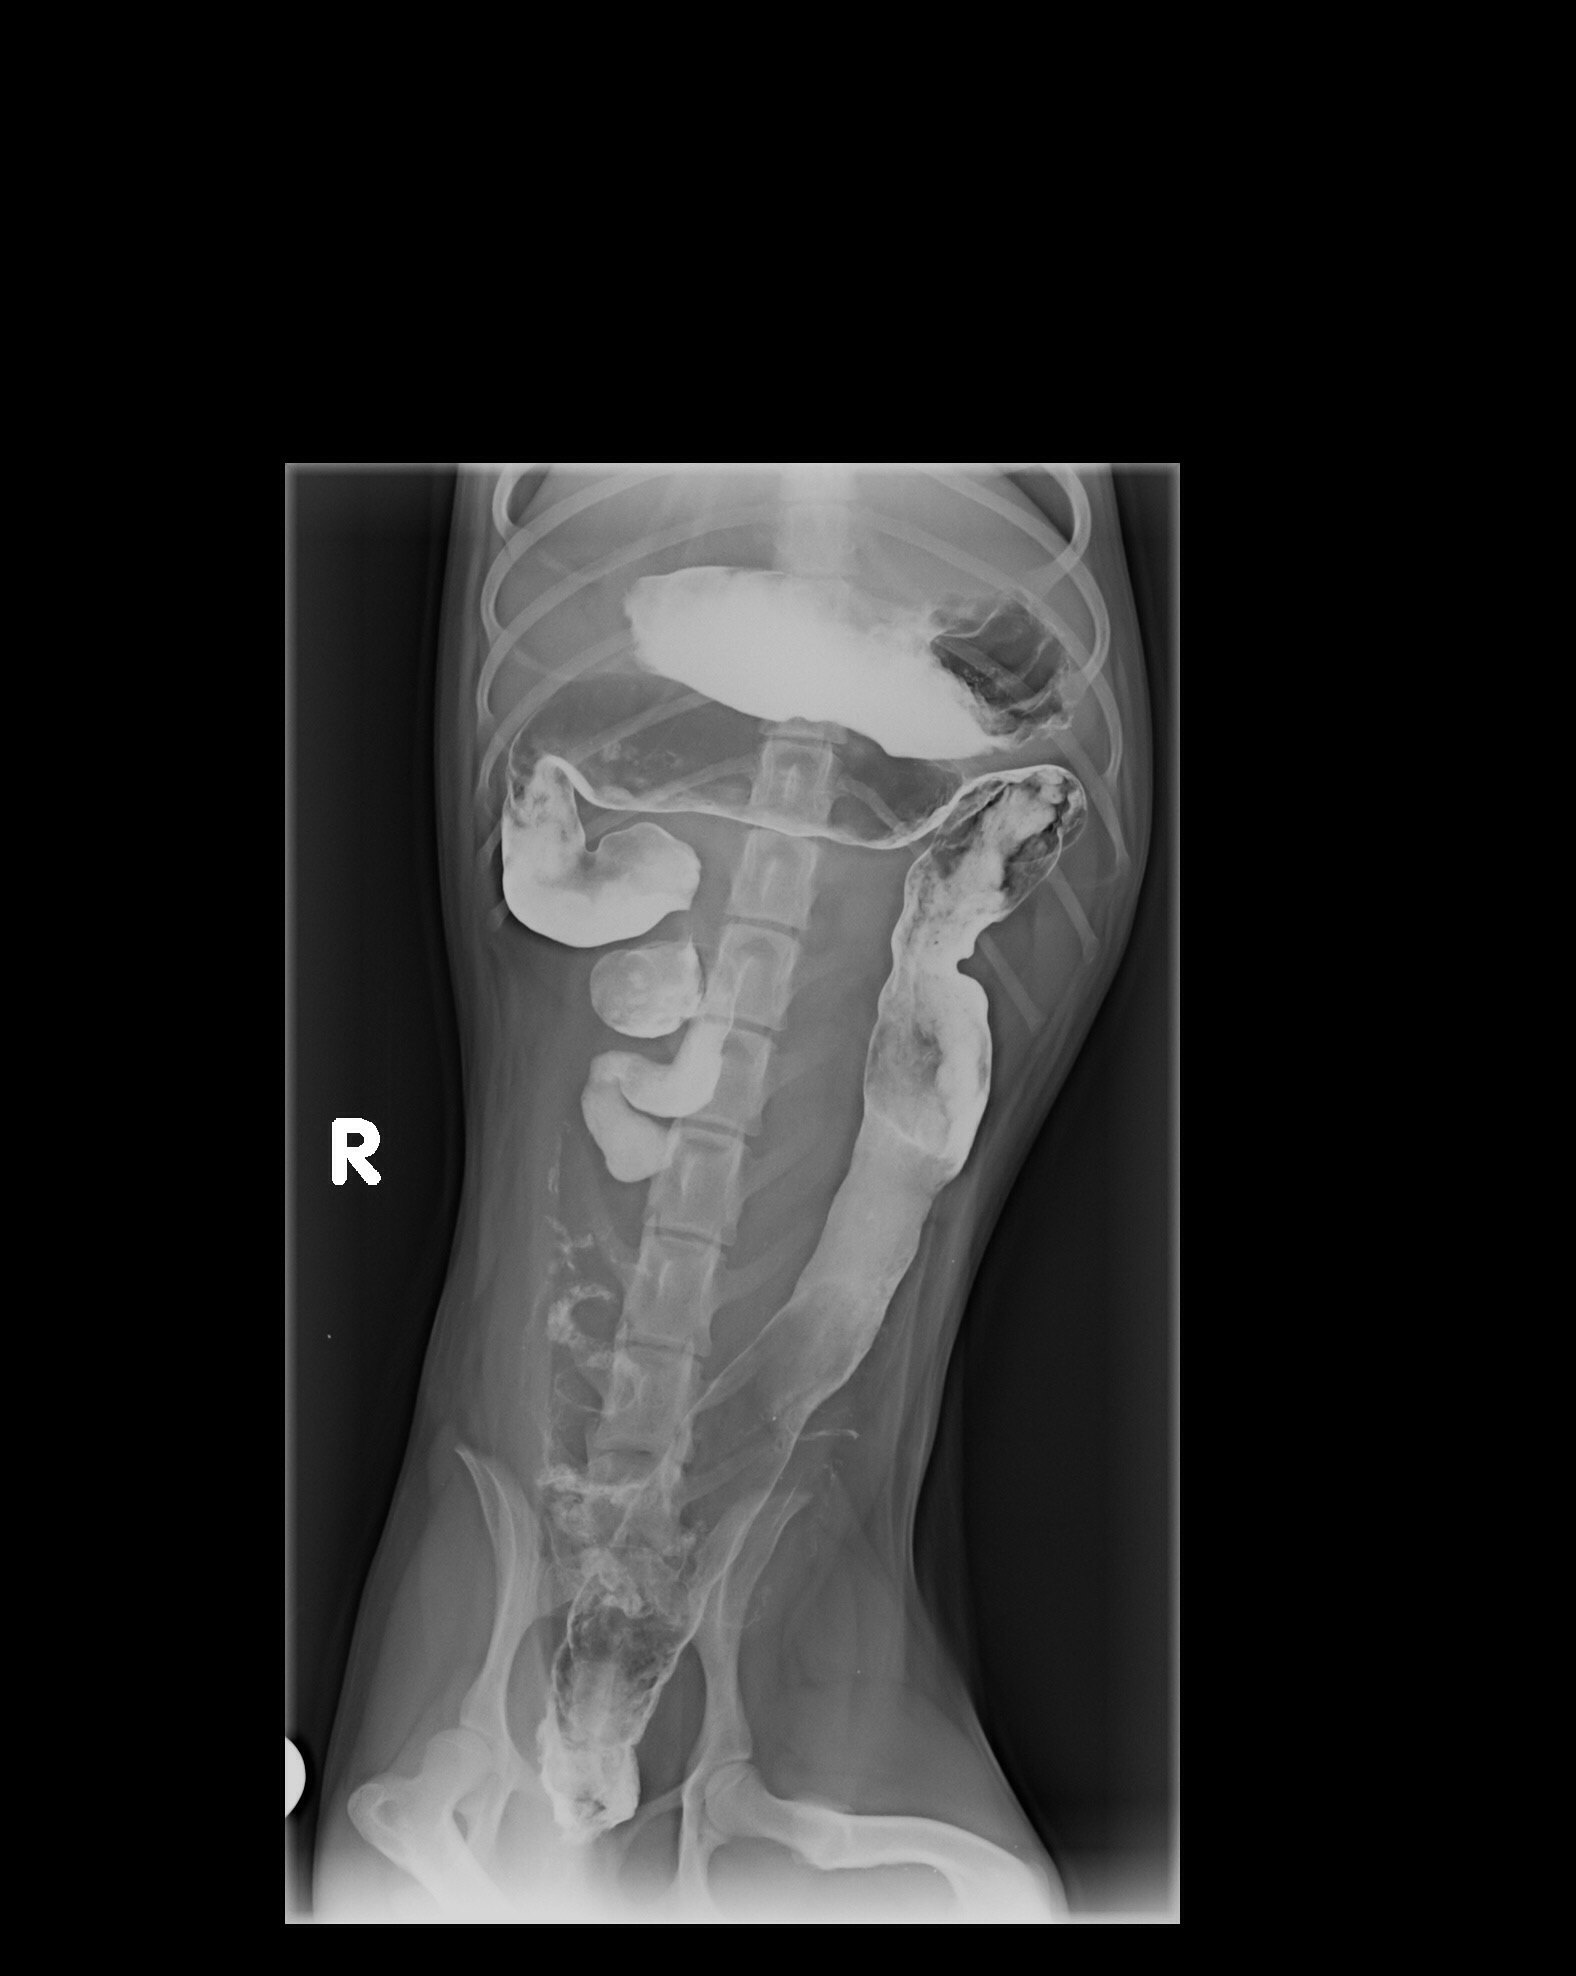

ديروز من بردمش دكتر و اونا نظرشون اين بود كه ممكنه چيزي قورت داده باشه و توي شكمش گير كرده باشه. سوفي xray شد و گفتند مقدار زيادي گاز توي شكمش هست، بهش berim contrast دادن و يكساعت بعد دوباره xray گرفتن و فقط مقدار كمي از كانترست خارج شده بود كه ميگفتن طبيعي نيست بايد خارج ميشده، صبح باز هم xray شد و بيشتر كانترست خارج شده بود ولي ميگفتن چون هنوز كمي اش مونده ممكنه چيزي باشه و بايد عمل بشه، اما من هنوز متقاعد نشدم، آيا واقعا اگه چيزي بود نبايد توي سه بار عكس گرفتن اونم بعد كانترست نباد نشون بده؟ سوفي بينهايت آب بدنش كم شده و واقعا نياز به سرم داره، ديگه بالا نياورده اما تا ديشب اسهال داشت. اونا بيست و چهار ساعت براي عكس نگهش داشتن تازه امروز گفتن بايد بيست و چهار ساعت ديگه بمونه براي سرم، اينجوري من فقط شارژ ميشم بدون اينكه مطمئن باشم قضيه چيه و اين كوچولوي زبون بسته هم هنوز حالش خوب نيست، من جواب ها رو براتون ايميل ميكنم، اگه نظرتون رو بگيد واقعا مديونتون ميشم.